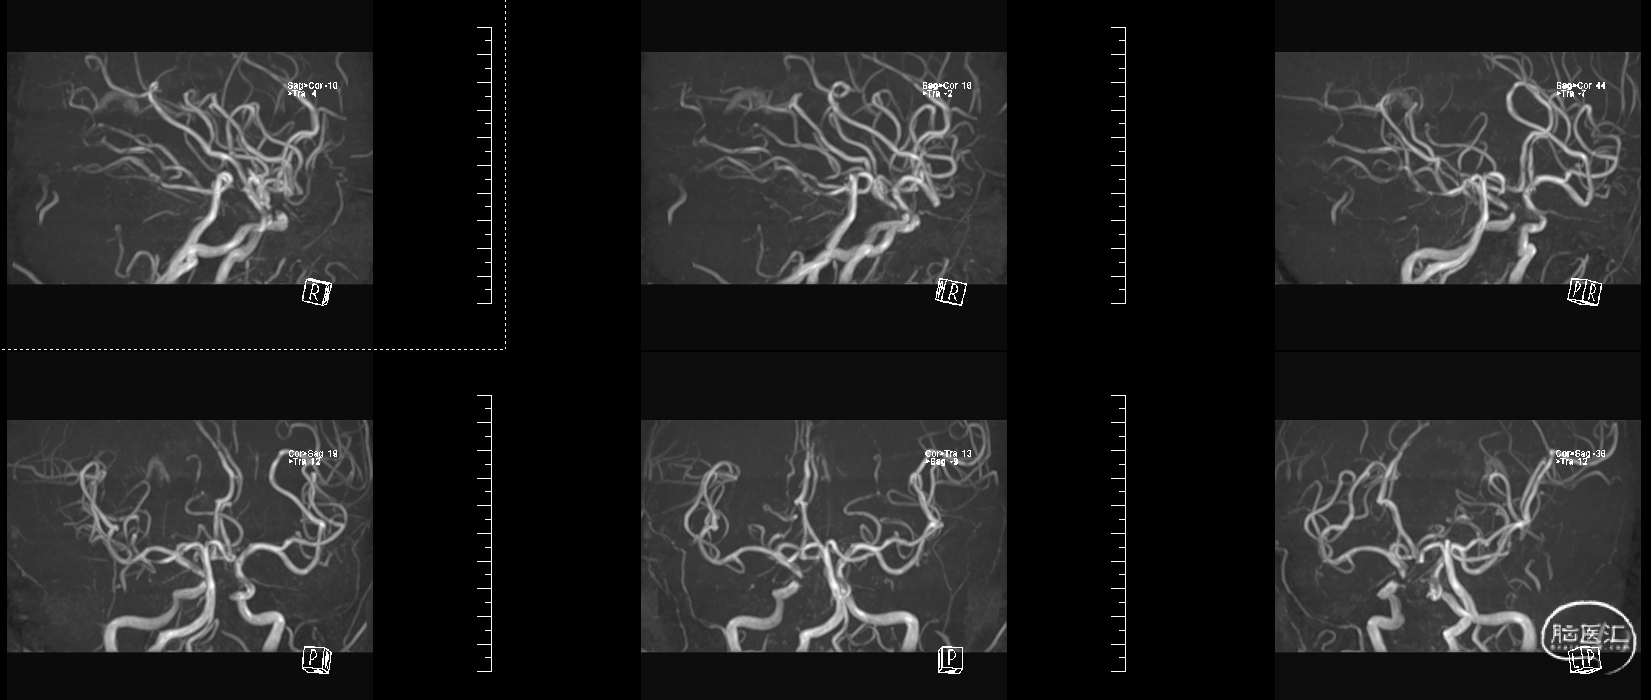

头颅MRI:左侧额顶叶急性脑梗塞;桥脑左份、双侧基底节、右侧脑室旁及双侧额叶多发腔隙性脑梗塞;双侧脑室旁及额顶叶轻度白质脱髓鞘;双侧上颌窦、筛窦、蝶窦炎;脑MRA示①右侧椎动脉纤细(变异)②左侧大脑后动脉P2段局部狭窄③左侧颈内动脉眼段局部严重狭窄④脑动脉轻度硬化改变,请结合临床及其他检查协诊。

溶栓同时急查头颅MRA

入院脑血管造影:

3、入院后查脑血管造影提示:左侧颈内动脉眼段重度狭窄。